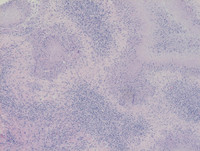

Cat Scratch Disease-H&E High Power

Category: Lymph Node and Spleen: Reactive/infectious > Infectious processes > Granulomatous, Necrotizing > Cat Scratch Disease

See reference case "Cat Scratch Disease" for details.